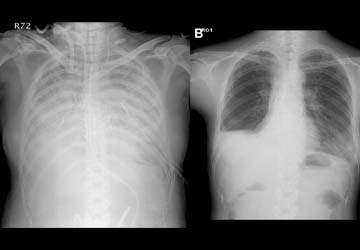

History: a 75 year old man status post partial left upper lobectomy, complicated by pneumothoraces status post chest tube placemente, presented with diffuse crepitus.

A chest radiograph was performed and is shown below. Radiographs: Diffuse subcutaneous emphysema and pneumomediastinum. Patchy basilar opacities In keeping with atelectasis and a probable small amount of left pleural fluid. Small biapical pneumothoraces

Chest CT: Extensive postoperative subcutaneous emphysema and pneumomediastinum. There is a moderate left-sided pneumothorax after left upper partial lobectomy, despite the presence o left chest tube with its lip at the left ape